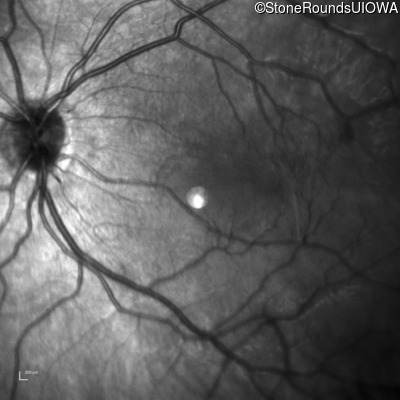

Infrared Fundus Photograph - Right - 20/2000

Exemplar